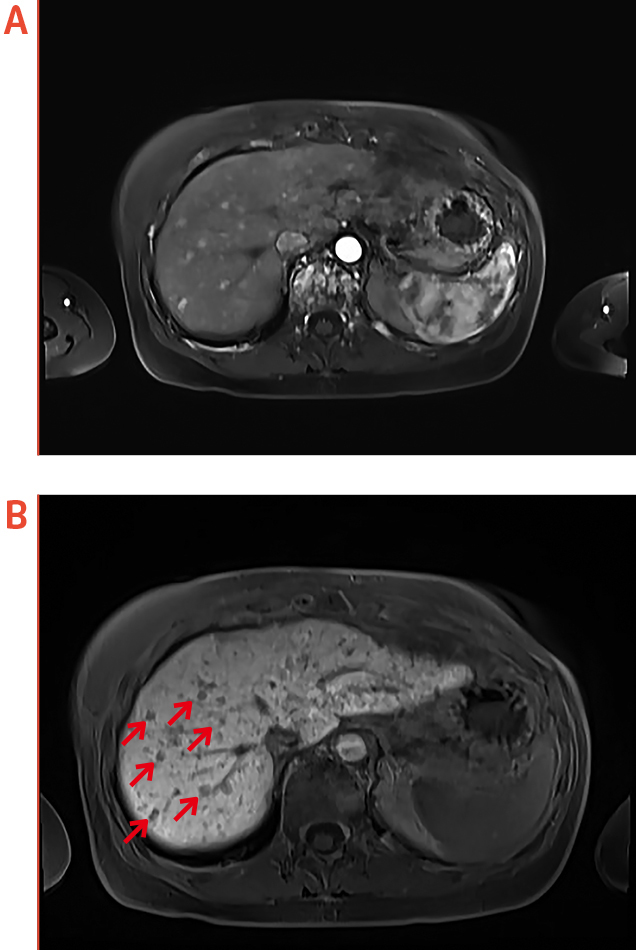

In the second case shared by Dr. Ka, the patient with history of breast cancer was presented with deranged liver function. While FDG-PET reflected no significant abnormality in the liver, the patient received additional EOB-MRI examination. Remarkably, EOB-MRI showed numerous sub-centimeter enhancing foci which are hypointense in HBP, suggesting the occurrence of liver metastasis.

Figure 2. Liver metastasis identified by EOB-MRI, (a) axial arterial phase, (b) axial HBP

(red arrows indicate hypointense foci, images provided by Dr. Ka)